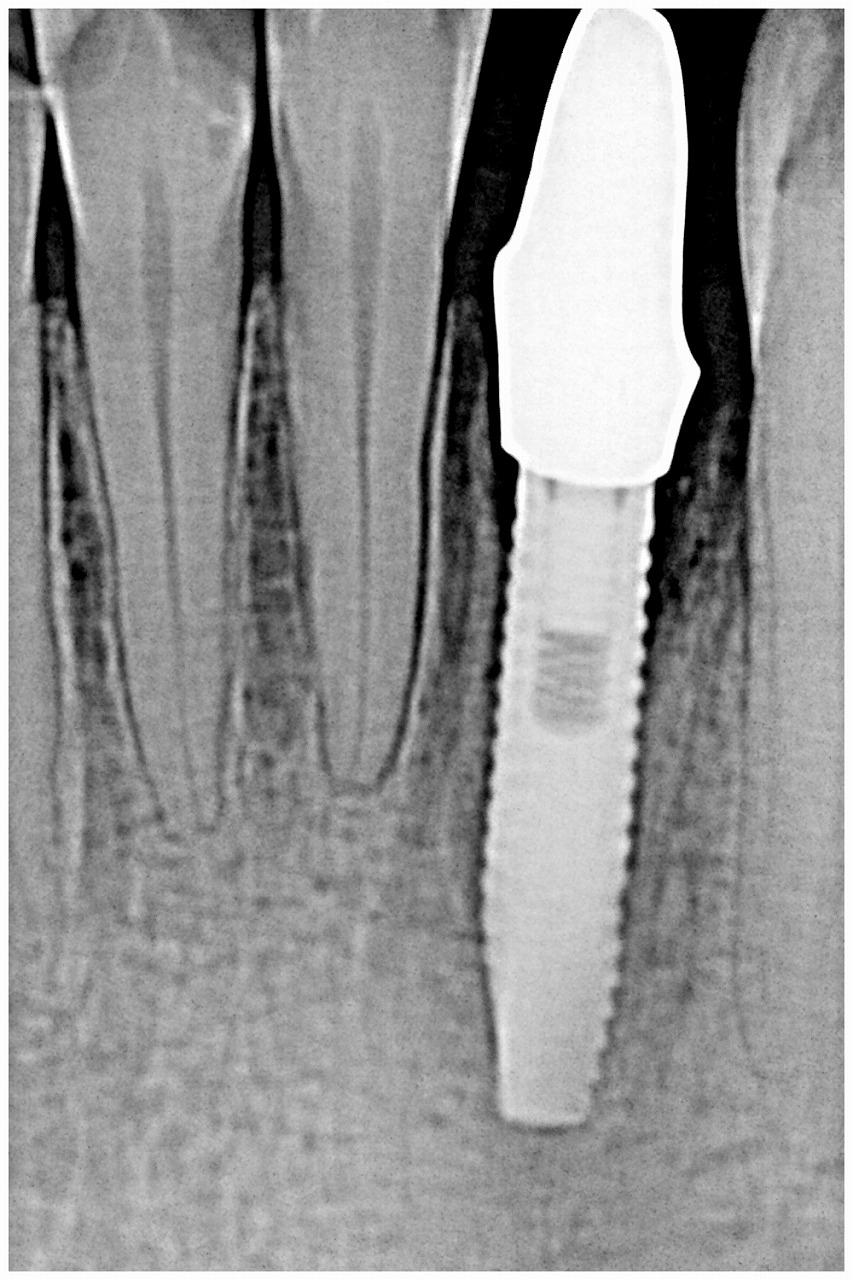

印象時のデンタルレントゲンになります

プロビジョナルになります

最終補綴になります

歯を抜いているにも関わらず歯茎下がりもなく綺麗に仕上がっています